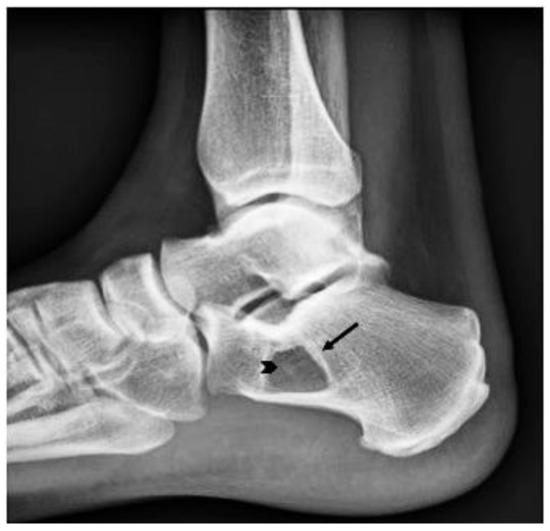

Allogenic Cancellous Bone versus Injectable Bone Substitute for Endoscopic Treatment of Simple Bone Cyst and Intraosseous Lipoma of the Calcaneus and Is Intraosseous Lipoma a Developmental Stage of a Simple Bone Cyst?

by Andreas Toepfer, Michael Strässle, Ulrich Lenze, Florian Lenze and Norbert Harrasser

Simple bone cysts (SBCs) and intraosseous lipoma (IOL) of the calcaneus are rare tumor entities that are primarily diagnosed due to unspecific heel pain, incidental findings, or rarely due to pathological fractures. Compared to traditional open tumor resections, endoscopic resection of these benign [...] Read more.

Simple bone cysts (SBCs) and intraosseous lipoma (IOL) of the calcaneus are rare tumor entities that are primarily diagnosed due to unspecific heel pain, incidental findings, or rarely due to pathological fractures. Compared to traditional open tumor resections, endoscopic resection of these benign tumors aims to minimize surgical morbidity and maximize surgical efficiency without compromising safety. Grafting is regularly performed to reduce the risk of recurrence and stimulate osseous consolidation of the lytic lesion. As the incidence is low and treatment strategies are heterogeneous, there is no clear consensus for the treatment of simple cysts or intraosseous lipomas of the calcaneus. The objectives of this study are (a) to present medium to long-term results after endoscopic resection and grafting with allogenic cancellous bone or bioresorbable hydroxyapatite and calcium sulfate cement, and (b) to add further evidence to the discussion of whether calcaneal SBC and IOL are the same entity at different developmental stages. Between 2012 and 2019, a total of 25 benign bone tumors consisting of 17 SBCs and 8 IOLs were treated by A.T. with endoscopic resection and grafting, comprising the largest cohort to date. For grafting, 12 patients received allogenic cancellous bone (group A) and 13 patients received injectable bone substitute (group B). Pre- and postoperative imaging using plain X-rays and MRI was retrospectively analyzed with a mean follow-up time of 24.5 months to assess tumor size, osseous consolidation (modified Neer classification), and tumor recurrence. A retrospective chart analysis focusing on adverse intra- and perioperative events and other complications associated with the surgical procedure was performed using the modified Clavien–Dindo classification (CD1-3). A total of 12/13 cases with allogenic bone grafting showed a Neer Type 1 osseous healing of the tumorous lesion after endoscopic resection, whereas only 5/11 cases with injectable bone substitute showed sufficient healing (types 1 and 2). There were three recurrent cysts (Neer 4) and two persistent cysts (Neer 3) after using injectable bone substitute. Two CD1 complications were observed in group A (prolonged wound drainage, sural neuritis) and eight complications were observed in group B (6× CD1, 2× CD3). At least two IOLs diagnosed preoperatively using MRI were ultimately identified as SBCs upon histopathologic examination. Allogenic cancellous bone grafting after endoscopic resection of calcaneal SBC or IOL showed a very low rate of complications and no tumor recurrence in our series. On the other hand, depending on the material used, injectable bone substitute showed a high rate of “white-out” (excessive drainage), resulting in multiple complications such as prolonged wound healing, insufficient permanent defect filling, recurrence, and revision surgery. Over time, calcaneal SBC may transform into IOL, exhibiting distinct features of both entities simultaneously during ossoscopy and histopathological analysis. Full article